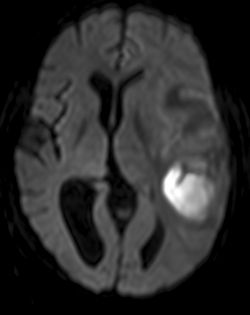

Hvorledes ser en cystisk tumor ud på diffusionsvægtet MR?

CT DWI ADC

En cystisk tumor er mørk på DWI og lys på ADC